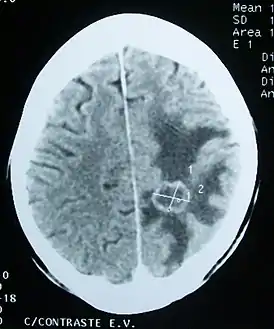

![]() Отёк вещества головного мозга (тёмный участок) вокруг метастатической опухоли (компьютерная томограмма) | |